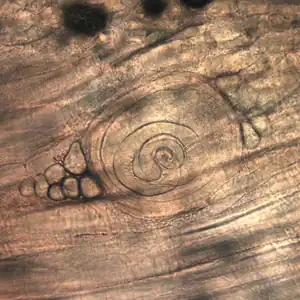

| Trichinella larvae in pressed bear meat, partially digested with pepsin. The classic coil shape is visible. | |